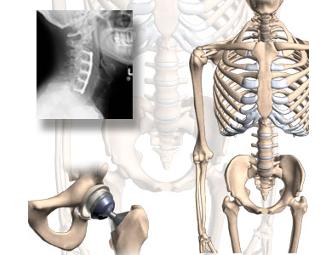

Orthopedic Evaluation & Treatment

This is a sport-specific musculoskeletal evaluation by Dr. Kohler-Ekstrand, an orthopedic surgeon at the 100 UCLA Plaza. Weaknesses will be determined as well as physical therapy exercises given and explained for strengthening.